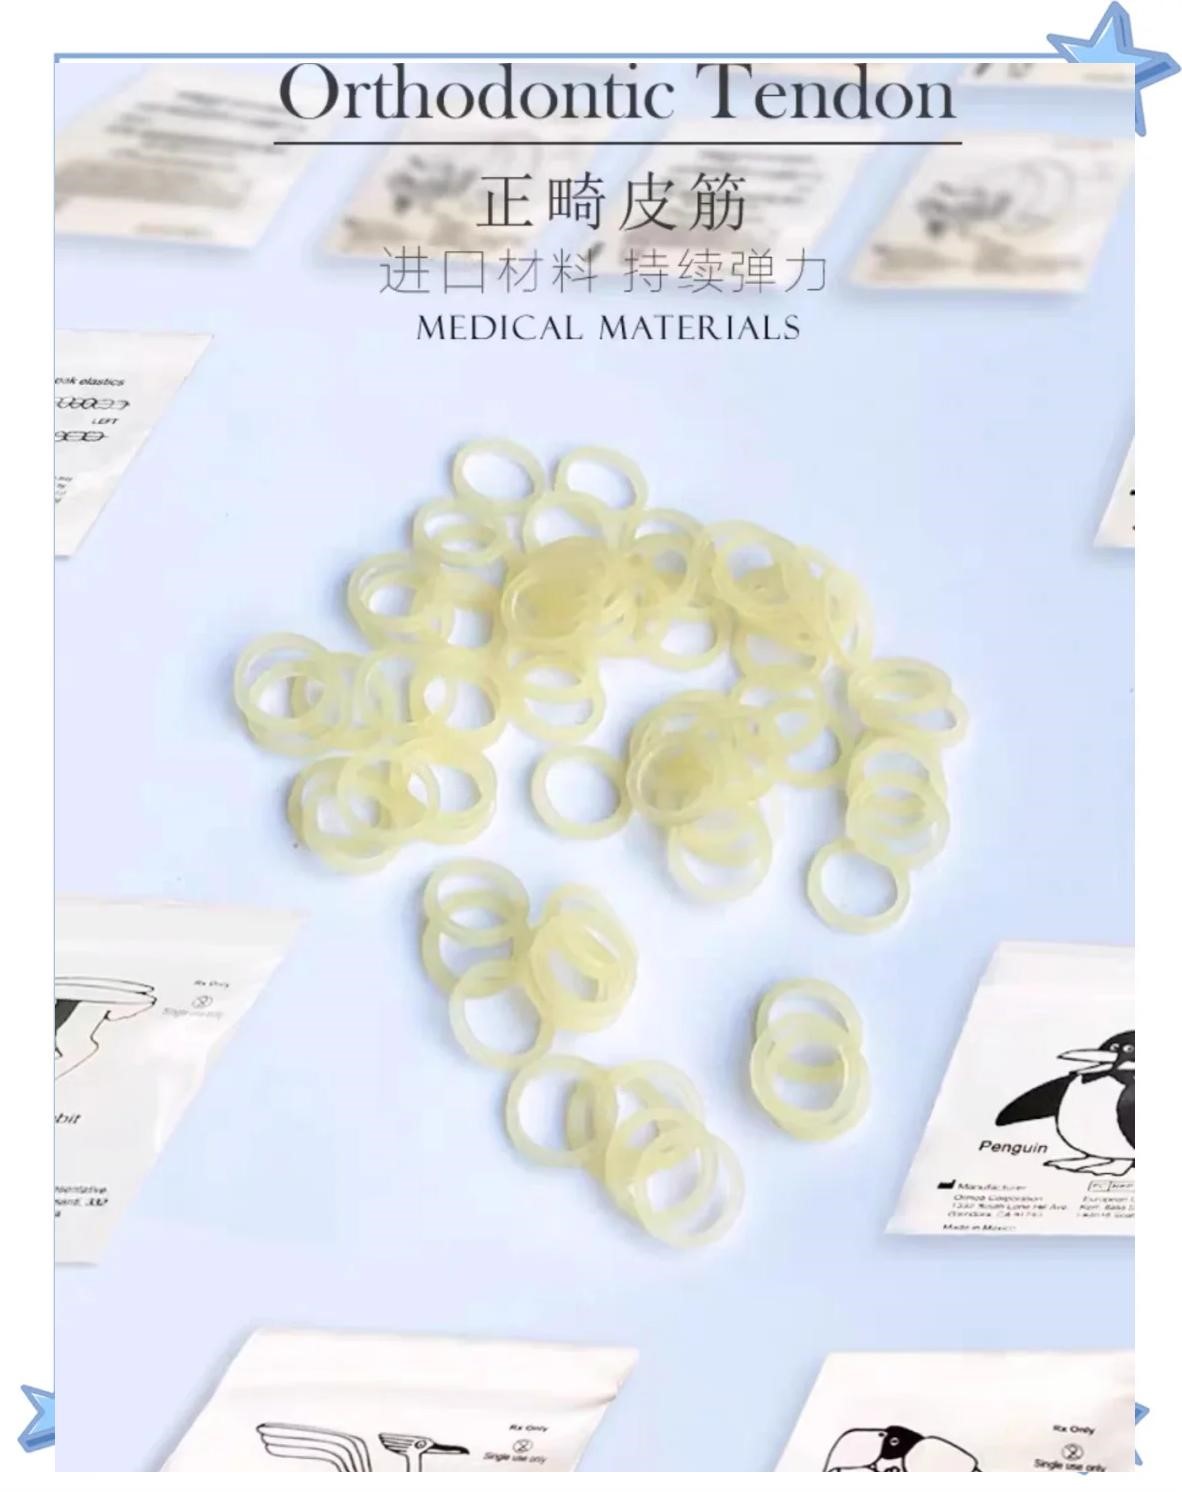

3. 牵引部件 - 力量的“传输带”

正畸弹力圈:一端挂在口内装置的拉钩上,另一端挂在口外面具的横杆上,从而将面具产生的向前牵引力精准地传递到上颌骨和牙齿上。

* 最后,将弹力圈挂到口内拉钩和面具横杆上。前方牵引常用的弹力圈型号是“老虎”尺寸,一边挂2根,两边共4根,每天更换。